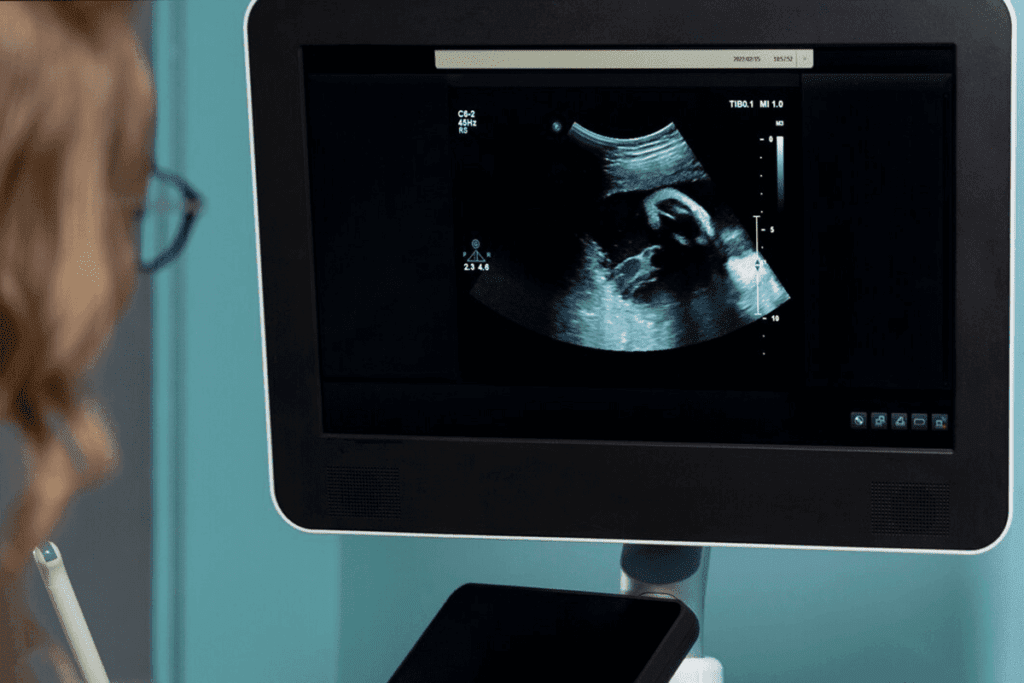

At 9 weeks, you might have some screenings and tests. These include blood tests for infections and blood type, and an ultrasound to check your baby’s heartbeat. First trimester screenings are key for finding genetic conditions and checking for pregnancy risks.